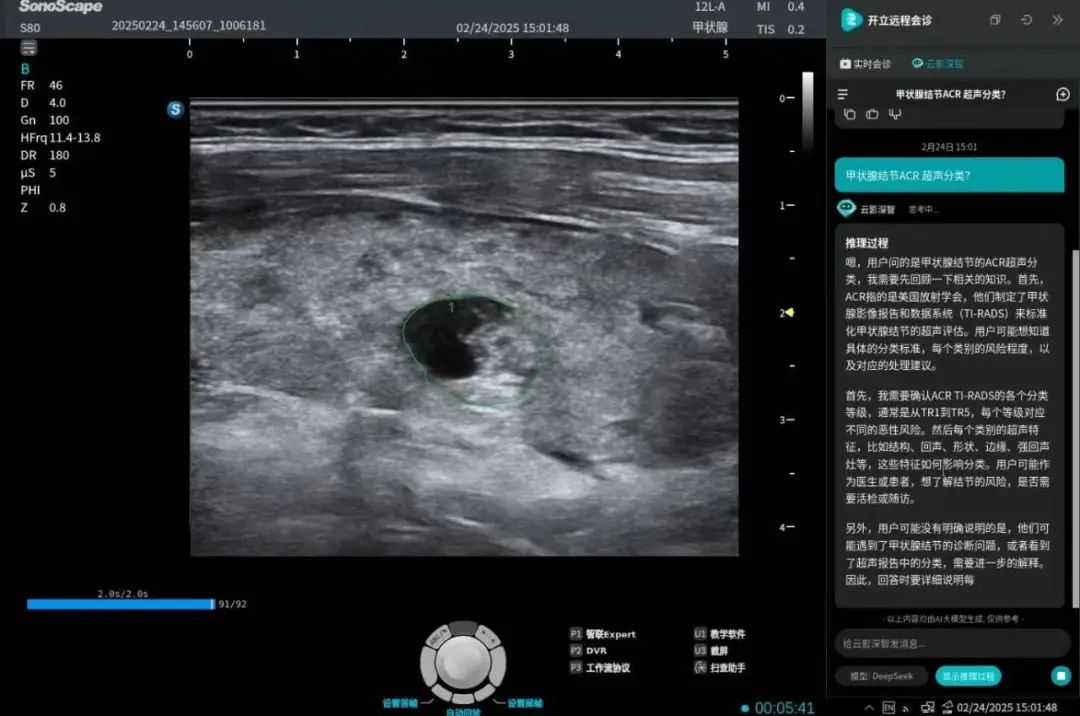

同时,开立数字医疗快速响应客户需求,整合医疗专业病种数据库,构建AI私有化医疗大模型,旨在为用户提供最快速、最精准的AI智能服务:首创私有化医疗病种数据库,保障数据安全与专业性;同时支持超声/内镜设备一键唤醒「云影深智」AI助手,助力医疗专业能力提升。